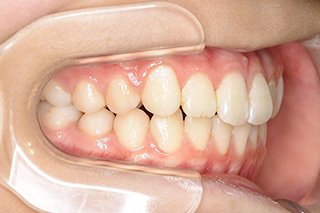

顎顔面矯正症例 11歳女児 Case

| 主訴 | 永久歯が変な所からはえてきている|顔貌 | |

|---|---|---|

| 施術内容 | 矯正1期治療 | |

| 治癒期間 | 1年5ヶ月間 | |

| 費用 | 459,200円(税込) | |

| リスク・ 副作用 | 痛みを伴う | |